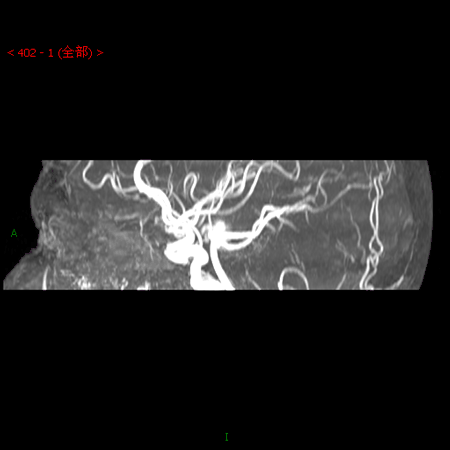

【正海-妙术视界】| 王勇教授:基底动脉 右侧大脑中动脉多发动脉瘤一

郭新宾:症状性左侧大脑中动脉重度狭窄血管成形术